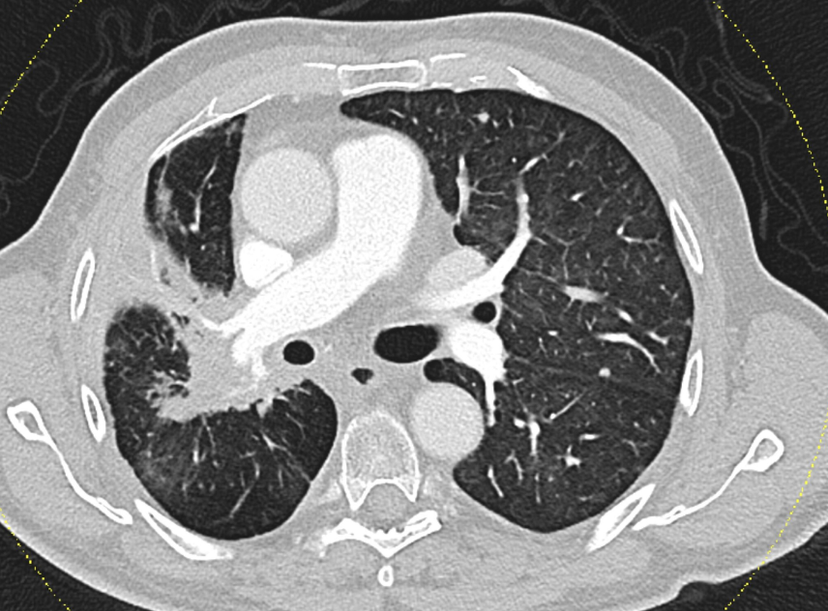

In total, 38.5% of participants developed pneumonitis. However, the rate was actually lower in the 70 Gy group, at 34.5%, compared to 50% in the group that received the lower dose. Only one case of more severe pneumonitis (grade 3) was reported, and it occurred in the lower-dose group. The survival data were particularly striking: in the high-dose group, more than 93% of patients were still alive one year after treatment – and that figure remained virtually unchanged at the four-year mark. By contrast, the median survival in the lower-dose group was 31 months, and tumour progression was more frequent in this group.

Radiation-induced lung damage was avoided thanks to careful and precise treatment planning. In both groups, the mean lung dose (MLD) was kept below the critical threshold of 20 Gy. “As long as clinicians adhere to established safety limits – especially in regard to low-dose lung volumes – we don’t expect to see an increased rate of pneumonitis,” says Dr Schragel. “These results clearly show that administering a higher radiation dose to the tumour does not necessarily mean a higher risk of inflammatory side effects – provided the treatment is well planned.”